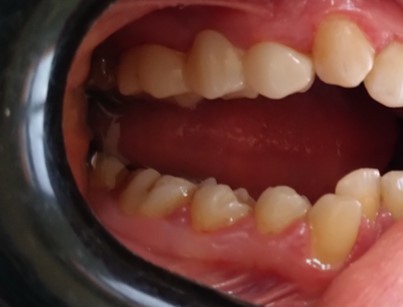

Crowns & Bridges

Before After

Before

After

Full E-MAX 4 crowns restoration